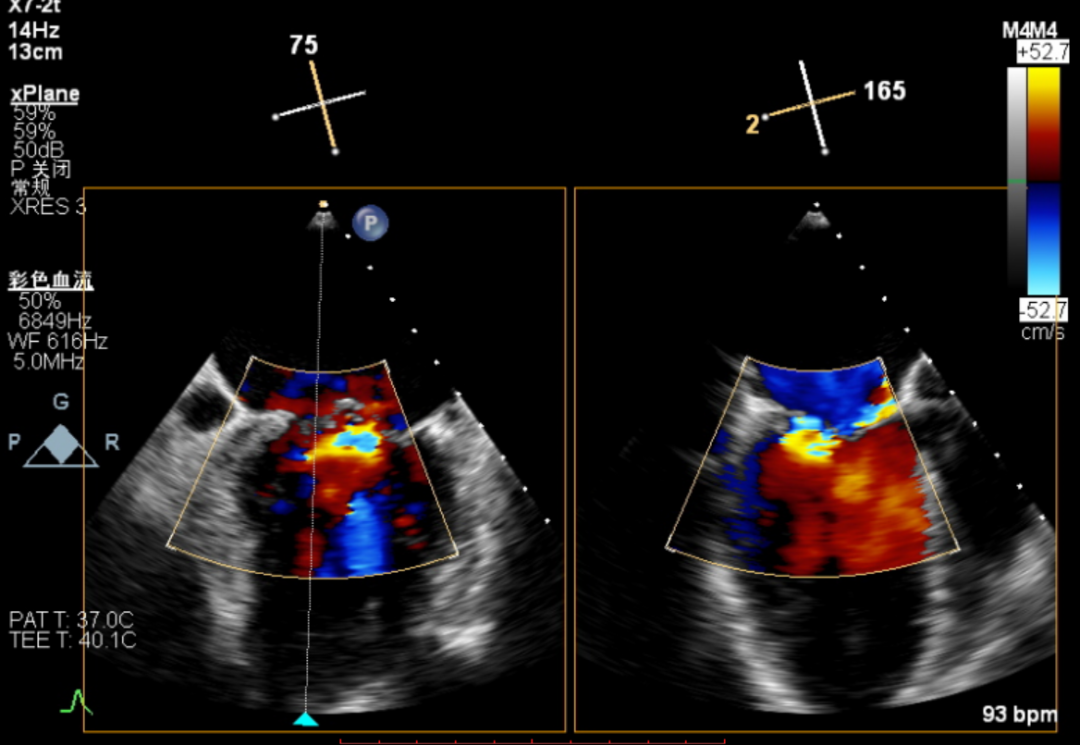

TEE显示,第二枚二尖瓣夹植入后反流减少

患者全麻后,在经食道超声心动图和X射线引导下,经股静脉入路,将申淇淇麟®系统瓣膜夹顺利送至二尖瓣瓣上区域,在超声辅助下夹闭二尖瓣病变区域(P3区域)。而夹闭后,患者的3区偏2区侧仍存在大量反流,方臻飞主任根据自身临床经验和患者情况进行充分评估后,决定释放二尖瓣夹合器,撒出输送系统、并进行第二次夹合。在超声引导并再次放入瓣膜夹输送系统,方臻飞教授凭借其精湛的手术技艺以及对器械特点的深刻理解,成功夹闭P2区域脱垂瓣叶,使反流量明显减轻。